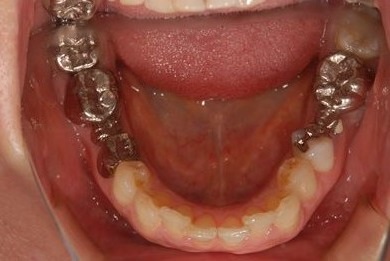

| 性別/年齢 | 女性 / 41歳 | ||||||||||||||||||||||||||||||||

| 治療方針 | セラミック治療にて、審美的回復を行う。 | ||||||||||||||||||||||||||||||||

| 治療内容 | エンプレスオールセラミッククラウン4本(オールセラミック用土台4本) | ||||||||||||||||||||||||||||||||